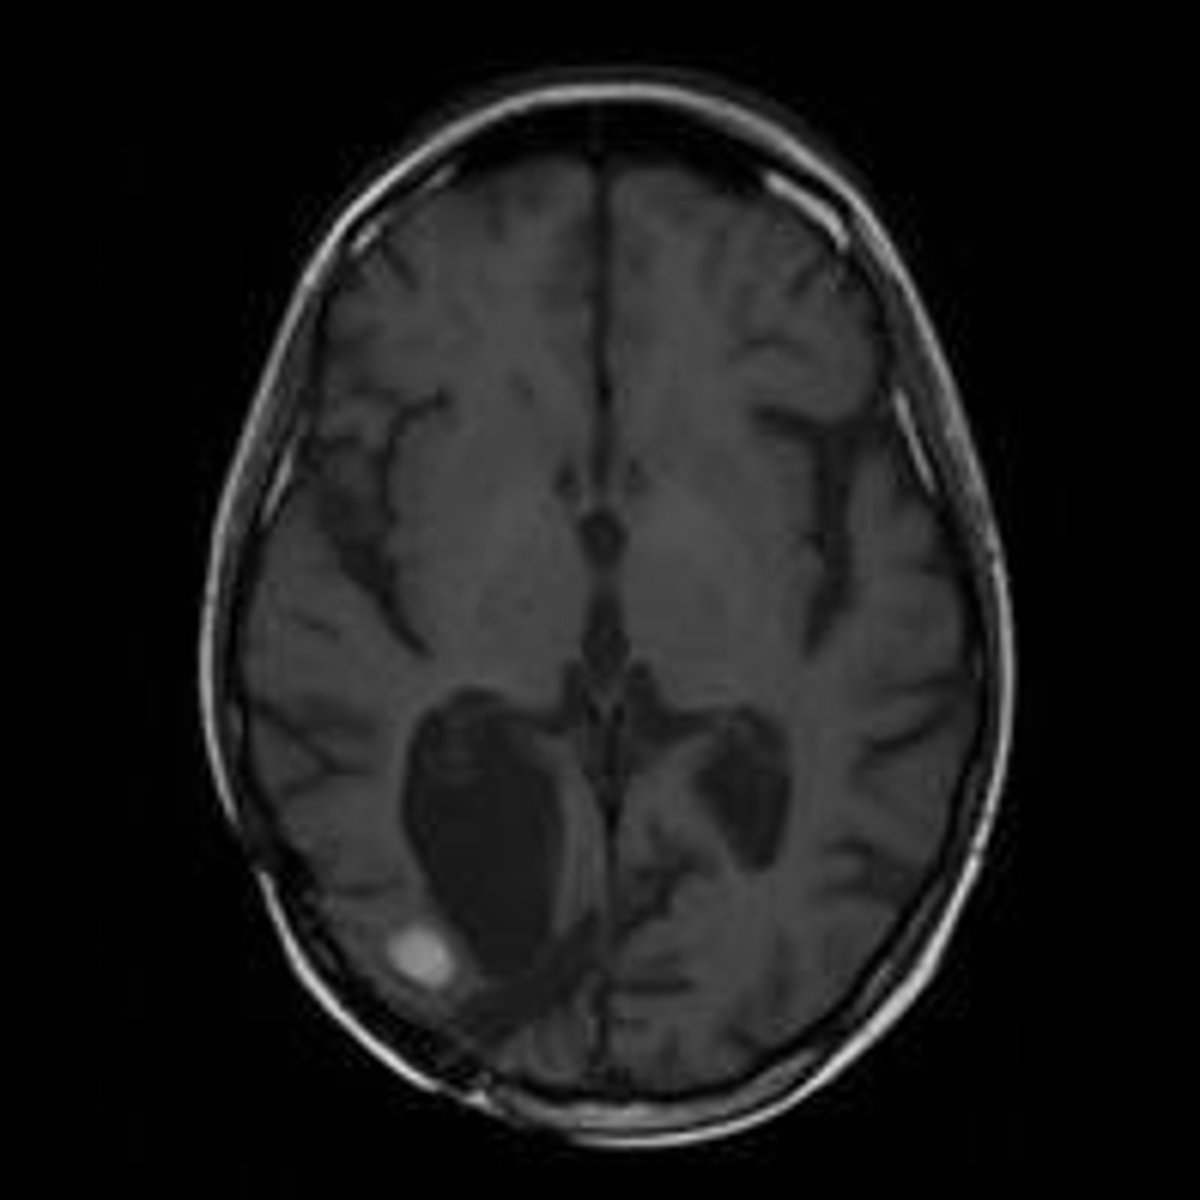

Resonancia Magnética De Un Cerebro Con Metástasis

Científicos del Instituto de Investigación Biomédica del Hospital Josep Trueta de Girona (Idibgi) han testado con éxito un nuevo contraste que mejora la visualización en resonancias magnéticas la extensión de los tumores cerebrales más agresivos.

Los científicos han comparado los resultados obtenidos entre el líquido de contraste convencional, el 'gadobutrol', con el 'gadofosveset', utilizado habitualmente para estudiar la aorta y los vasos ilíacos.

Los datos demuestran que el máximo nivel de información diagnóstica se logra seis horas después de haberse inyectado el contraste por vía intravenosa, cuando el tumor cerebral presenta "una definición no conseguida hasta ahora" y permite a los especialistas delimitar mejor su extensión.